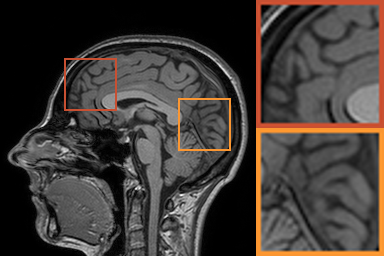

First, we test on 25 T1-weighted MRI data using three different undersampling patterns with a fixed 10% sampling rate. Fig. 3 shows the quantitative results (PSNR). Our method performances best for all three cases and has stronger stability compared with the second best method on variance. As for the effect of sampling ratios variation, we use radial mask under 10%, 30% and 50% sampling rates with evaluation of RLNE and MSE. Fig. 4 shows that our method has the lowest reconstruction error for all sampling rates. For more intuitive comparison, we illustrate the reconstruction error in term of pixels in Fig. 5. We also offer the qualitative comparison in Fig. 6. Visualized results demonstrate our method has better performance in both artifacts removing and details restoration. Time consuming is also considered. We compare our method with others on the 25 T1-weighted data using Radial mask with 10% and 50% sampling rate. Notice that ADMM-Net and ours are tested on GPU for the incorporation of deep architecture. Tab. 1 shows that our method provides an efficient reconstruction process and comes to the fastest method among the state-of-the-art competitors.

To demonstrate the robustness of our approach, we first apply it on various MRI data including the chest, cardiac and renal (?). In Tab. 2, Our proposed framework gives the highest PSNR for all of the tree types of MR images. Fig. 7 visualizes the corresponding results for chest data. we can see that our approach prevails over others in detail restoration at the junction of blood vessels as well as noise removal in the background. Actually, our method has a stronger ability to handle slight noise because of the subprocess of learning based optimization with deep prior. To demonstrate that, we add Rician noise at level of 20 to 25 T1-weighted MRI and 25 T2-weighted MRI to generate the noisy data. As what is shown in Fig. 8, our method over leads all the competitors by a large margin when the input is corrupted with Rician noise.